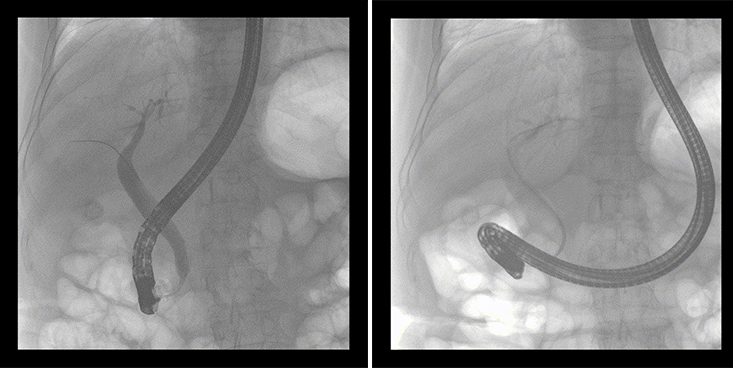

一位86歲的女性患者近來(lái)出現腹痛,入院后CT檢查并結合臨床表現被診斷為急性膽囊炎伴膽囊結石。經(jīng)專(zhuān)家團隊協(xié)商并與患者家屬溝通,決定對患者實(shí)施經(jīng)內窺鏡逆行胰膽管造影(ERCP)。

ERCP(經(jīng)十二指腸鏡下逆行胰膽管造影)現已成為比較成熟的微創(chuàng )介入技術(shù),被廣泛的應用于臨床,ERCP也是消化內鏡領(lǐng)域難度大、風(fēng)險大、技術(shù)復雜的微創(chuàng )手術(shù),其并發(fā)癥多為致命性,ERCP手術(shù)對醫生的要求很高,因此,ERCP醫生又被稱(chēng)為“刀尖上的舞者”。因為手術(shù)難度較大,過(guò)程復雜,需要C形臂精準的配合,對影像清晰度的要求也非常高。

普愛(ài)醫療移動(dòng)式平板中C為本次ERCP手術(shù)提供實(shí)時(shí)無(wú)損高清影像,幫助醫生精準定位?!俺上裥Ч浅0?!完全不輸國際大牌的醫學(xué)影像設備……”鼓樓醫院江北國際醫院內鏡中心手術(shù)團隊對普愛(ài)醫療移動(dòng)式平板中C的成像效果給與了高度的評價(jià)。

在消化內科主任的領(lǐng)導和多科室全力配合下,南京鼓樓醫院江北國際醫院成功完成了首例ERCP手術(shù)。